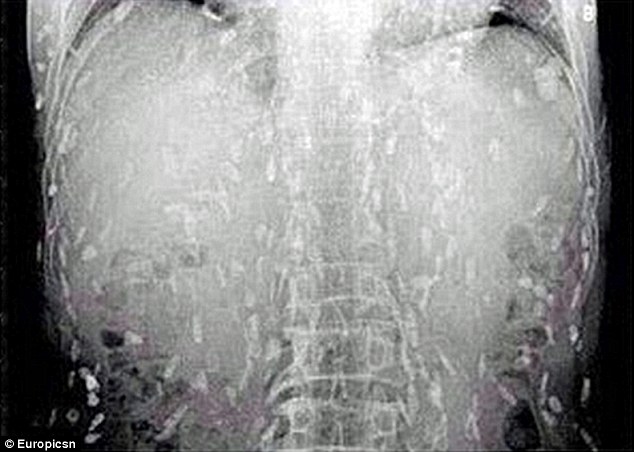

Προς έκπληξη του, οι αξονικές έδειξαν, ότι ολόκληρο το σώμα του είχε μολυνθεί με κυστοειδή σκουλήκια, επειδή έτρωγε πολύ σασίμι- ωμά κομμάτια ψαριού.

Ο άντρας από την Κίνα πήγε στον γιατρό, κάνοντας παράπονα ότι τον πονάει η κοιλιά του και έχει μεγάλη φαγούρα. Προς έκπληξη του, οι αξονικές έδειξαν, ότι ολόκληρο το σώμα του είχε μολυνθεί με κυστοειδή σκουλήκια, επειδή έτρωγε πολύ σασίμι- ωμά κομμάτια ψαριού.

Οι γιατροί πιστεύουν, ότι κάποια από τα ωμά ψάρια ήταν μολυσμένα.